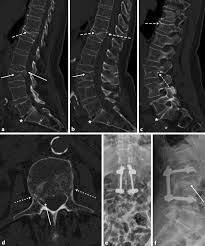

Die Postoperativen Komplikationen Und Die Rezidiv Bandscheibenvorfalle